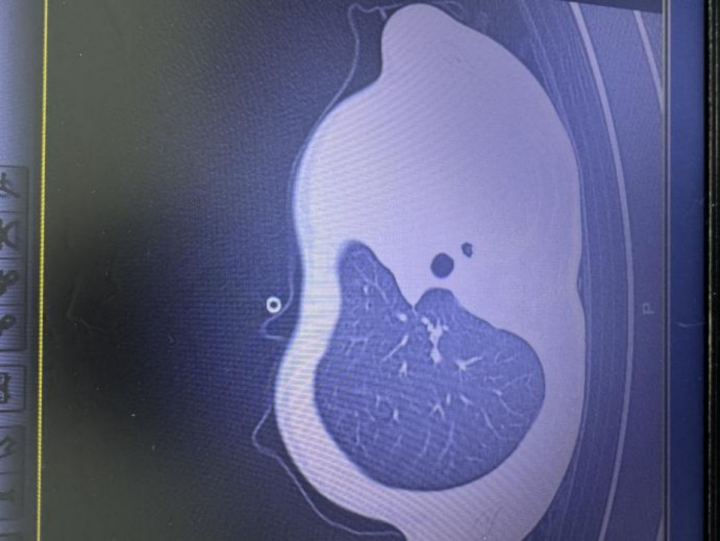

急诊查验效果让医护东说念主员俄顷弥留:验血透露炎症倡导大幅上涨,胸片发现左侧肺叶着实不职责了,影像学中变成大片白色,即时常所说的“白肺”,意味着肺功能严重受损,孩子也曾缺氧,随时有窒息危急。

图:影像透露肺白了一半